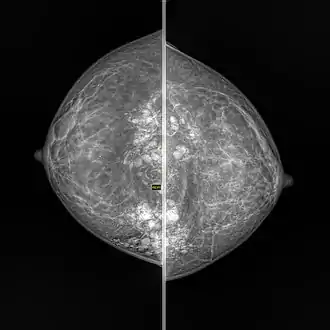

Snowball like hyperechogenic axillary lymph nodes in a woman with silicone implants removed due to complications